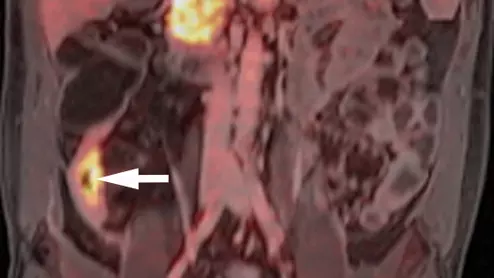

PET/MRI of FAPI radiotracer uptake in Crohn's disease

The FAPI radiotracer experts used in this research can bind specifically to the connective tissue cells that cause intestinal wall fibrosis common to Crohn's disease.